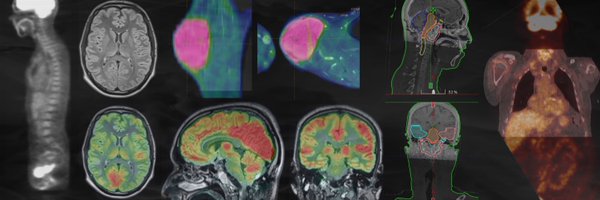

The Laboratory of Translational Imaging in Oncology (LITO) is a research unit (U1288) supported by @Inserm and @institut_curie. #Oncology #Radiomics #Biomarker

Amino acid PET is highly relevant in patients with either #Glioblastoma or metastatic #BrainCancer. https://t.co/32LGk43lf5

#MolecularImaging #PETscan @galldiks @ph_lohmann